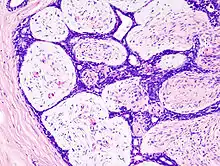

Histopathologic image of breast fibroadenoma. Core needle biopsy. H&E stain.

Microscopic

Fibroadenoma of the breast is a benign tumor composed of a biplastic proliferation of both stromal and epithelial components.[14][15] This biplasia can be arranged in two growth patterns: pericanalicular (stromal proliferation around epithelial structures) and intracanalicular (stromal proliferation compressing the epithelial structures into slit-like spaces).

These tumors characteristically display hypovascular stroma compared to malignant neoplasms.[16][17][11] Furthermore, the epithelial proliferation appears in a single terminal ductal unit and describes duct-like spaces surrounded by a fibroblastic stroma. The basement membrane is intact.[18]